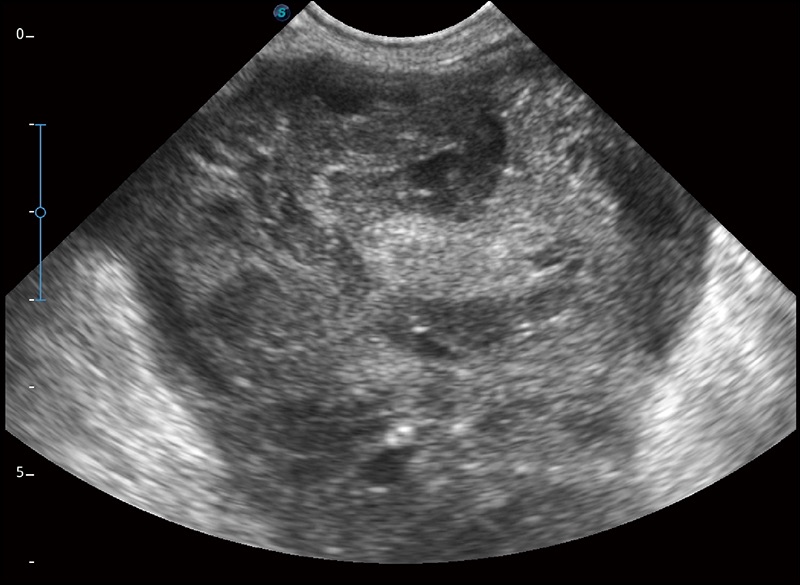

α1卓越的图像质量和便捷的工作流程,使每位宠物医生都能轻松扫查。其全面的兽用应用功能和紧凑型的结构设计,可以满足动物检查的多种需要。专业的预设检查模式和多领域测量软件包有助于为不同类型的动物提供检查, 让宠物医生能够出色的完成工作。

扩展成像

支持线阵和凸阵探头,一键操作即可获得更宽的图像视野